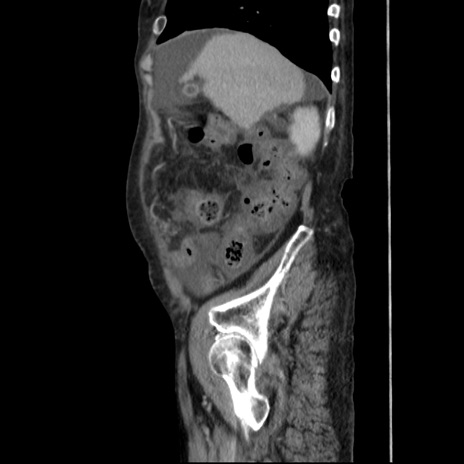

症例31(矢状断像)

【症例】80歳代 女性

【主訴】腹部膨満感

【現病歴】他院にて肝硬変にてフォロー中。1週間前から便秘、腹部膨満感、臍部腫瘤あり受診となる。

【既往歴】肝硬変

【身体所見】腹部膨隆あり、皮膚変化なし、疼痛なし。

【データ】WBC 4600、CRP 0.25

冠状断像